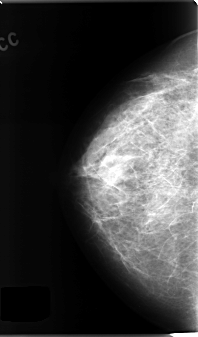

C_0136_1.RIGHT_CC

LEFT_CC LINES 4816 PIXELS_PER_LINE 2712 BITS_PER_PIXEL 12 RESOLUTION 50 NON_OVERLAY